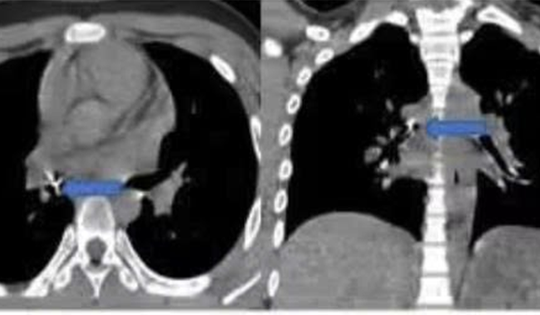

Chiếc răng gãy rơi vào khí quản khiến bé trai khó thở

29/12/2025 12:49

Bé trai 10 tuổi ho, khó thở sau tai nạn giao thông, bác sĩ phát hiện một chiếc răng gãy rơi vào khí quản suýt gây tắc đường thở.